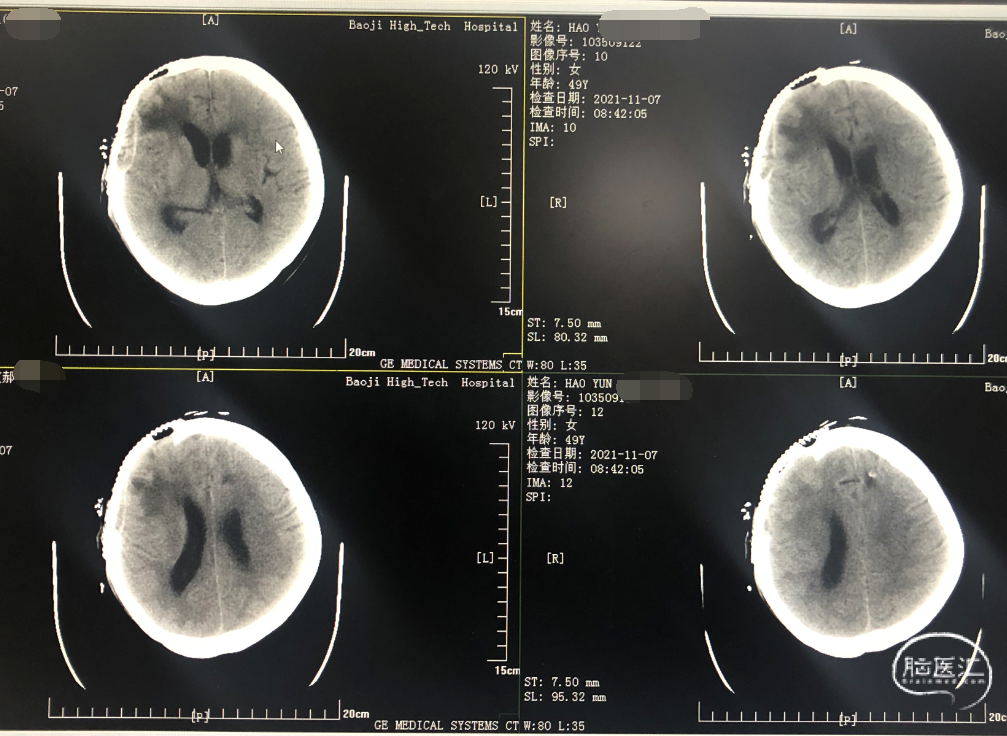

前头颅ct提示左侧丘脑出血破入脑室,左侧丘脑内侧和三脑室内均有血肿

脑内血肿ct图片

入院昏睡状,头颅ct提示枕叶出血,硬膜下血肿.